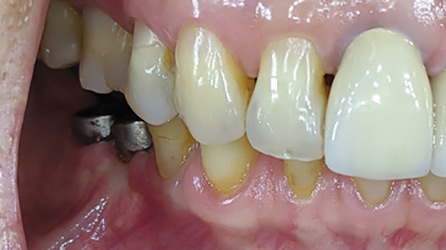

The Strategic Use of Compromised Teeth/Tooth Roots to Help Serve as Abutments for a Fixed Provisional Prosthesis During Implant Reconstruction

Belcastro-thumbnail alternate text for this image

Convenient Engineering’, a term coined by Michael Cohen ‘Interdisciplinary Treatment Planning, Quint Dec. 2011’, states that “while planning cases on ‘auto-pilot’ may save time and money and may be compatible with both the wishes of the dentist and the patient, it may also be thought of as ‘CONVENIENT ENGINEERING’ and is not necessarily in the … Read more